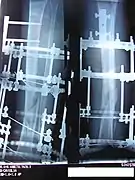

An Ilizarov apparatus treatment for the fractured tibia and fibula bones of the right leg.

The photographs and radiographs illustrate the application and emplacement of an external fixator, an Ilizarov apparatus, to repair the open fracture of the lower left leg of a man. The photographs were taken four weeks after the patient fractured the shinbone (tibia) and the calfbone (fibula) of his left leg, and two weeks after the surgical emplacement of the Ilizarov apparatus to immobilise the leg and isolate the wound and fracture site to facilitate healing.